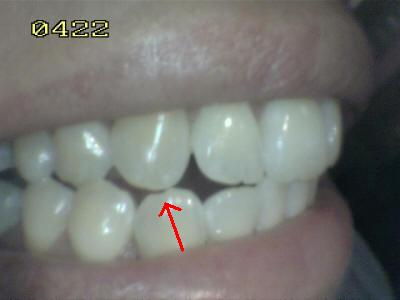

En apariencia una relación

canina normal (guía anterior)

Observe el desgaste del canino inferior,

que no cumple la función de guía canina, y la función de

grupo posterior de premolares y hasta del primer molar. |

Por falta de guía canina en el lado de

trabajo, hay un desgaste de los bordes incisales del lateral

y central |